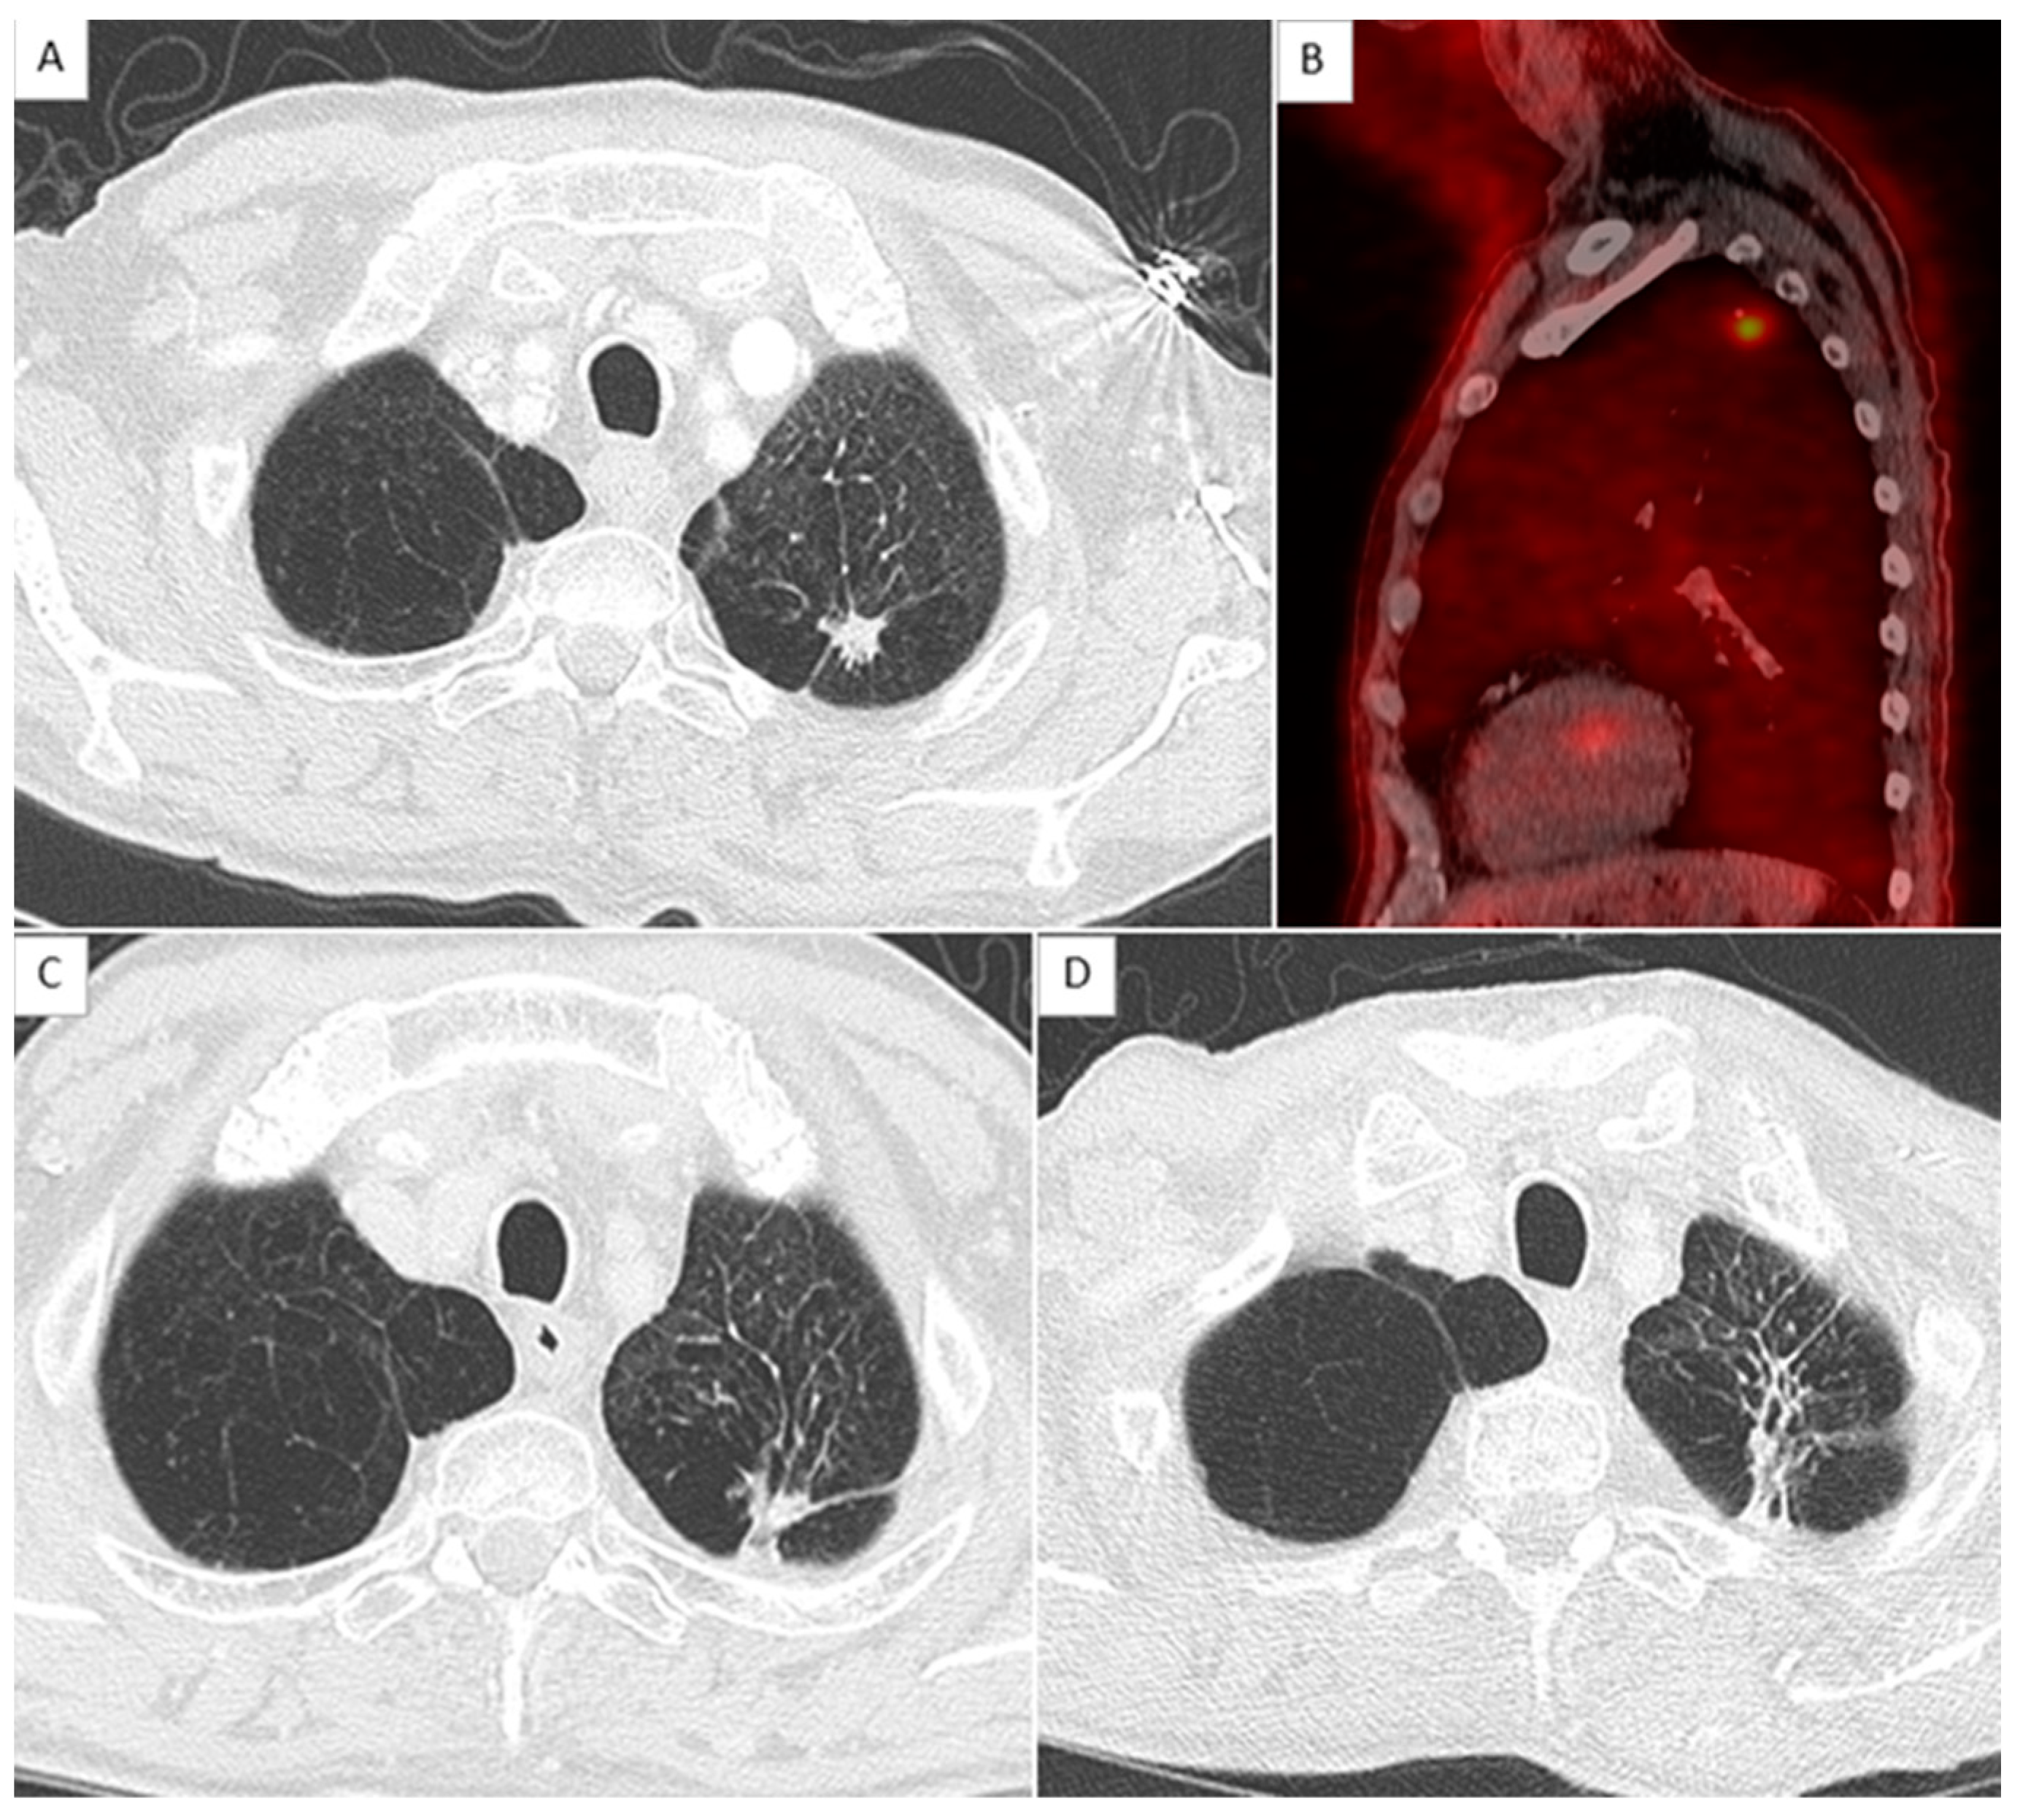

2.4. CT Scan Monitoring

2.5. Local Relapse Definition